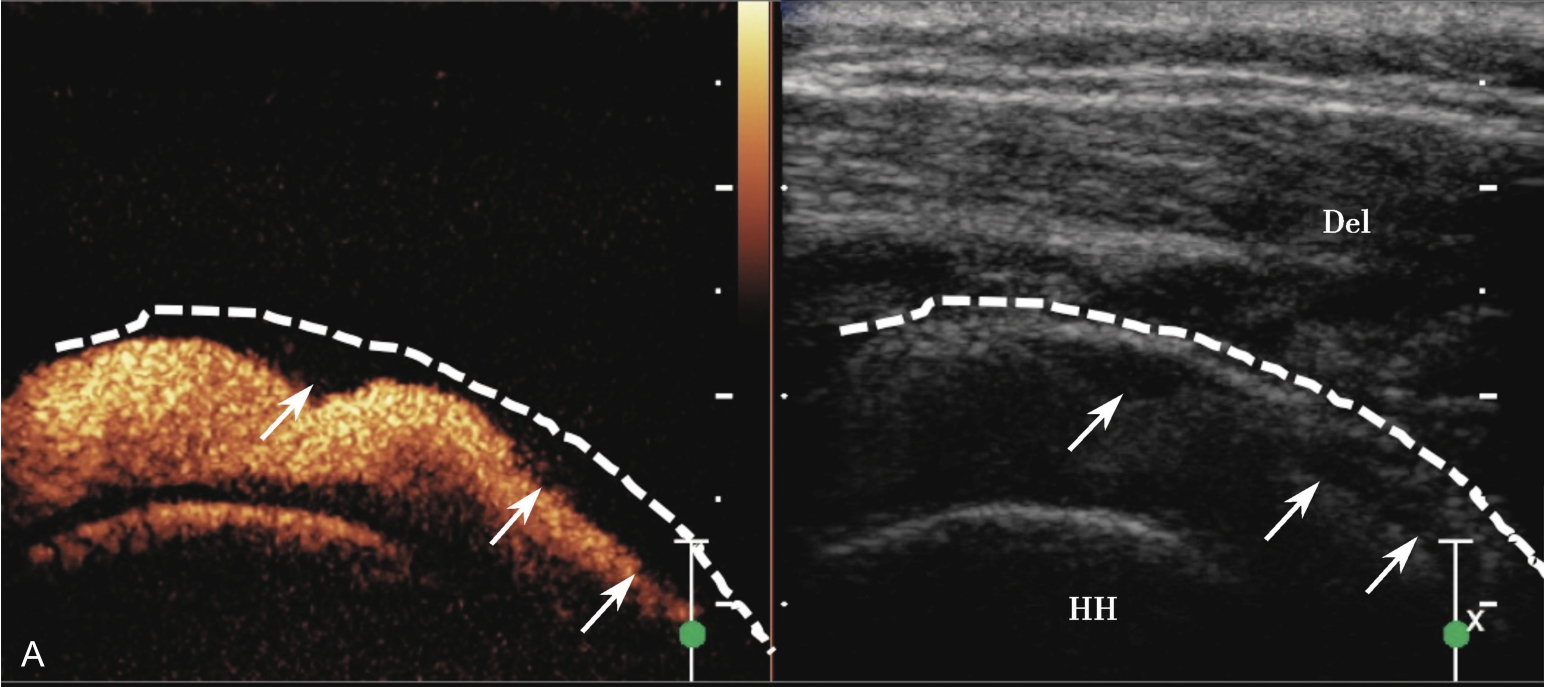

▲ 图2-6-8 超声引导下关节腔造影

A.注入生理盐水及造影剂混合液后关节腔内充盈缺损(增厚的关节囊,箭头所示);B.关节腔内粘连带形成(箭头所示);虚线:关节囊;HH:肱骨头;Del:三角肌